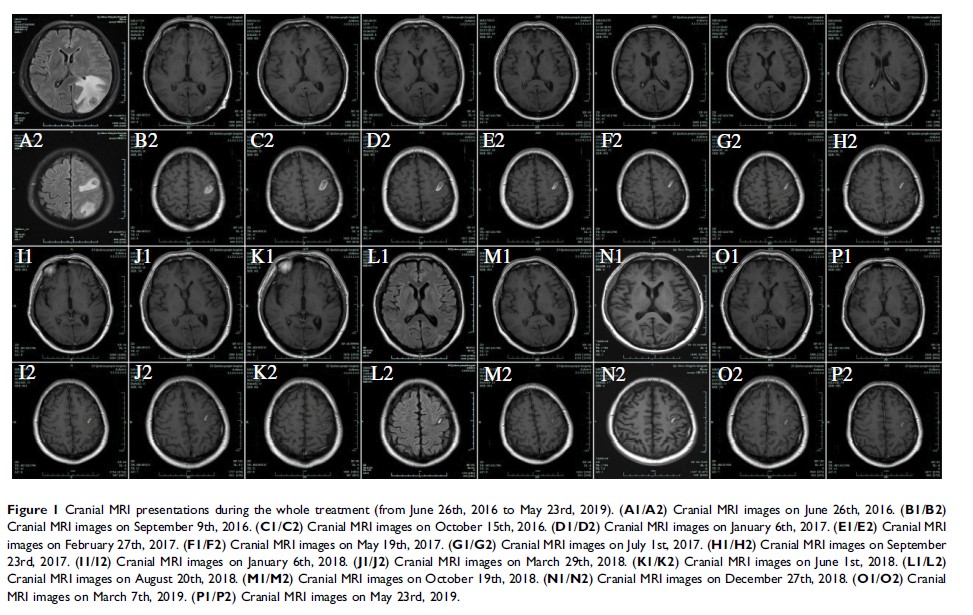

伴有症状性脑转移的肺腺癌在系统治疗后的放射学完全缓解:病例研究